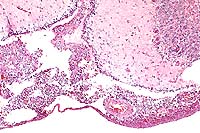

Case 3-3. Cerebellum. Heterophils and mononuclear cells infiltrate the leptomeninges. 10X

AFIP Diagnosis: Brain: Meningoencephalitis and ventriculitis, heterophilic, subacute, moderate, with bacilli, turkey, avian.

Contributor's Diagnosis and Comments: Severe heterophilic leptomeningitis, ependymitis and periependymal encephalitis (ventriculitis), with abundant bacteria. Edema and malacia, cerebellum.

Although ependymitis can occur associated with any bacterial leptomeningitis, the prevalence of this change in these birds was striking, and is similar to that reported in the literature. Some specimens contain sections of cerebellum that are affected by edema and early malacia. These lesions are not unlike those of avian encephalomalacia and may have a vascular basis, but only the cerebellum was affected for an unknown reason. The grower apparently recognized infection in the source flock from eggs but was attempting to salvage birds hatched prior to a convenient time for decontamination of the facility.